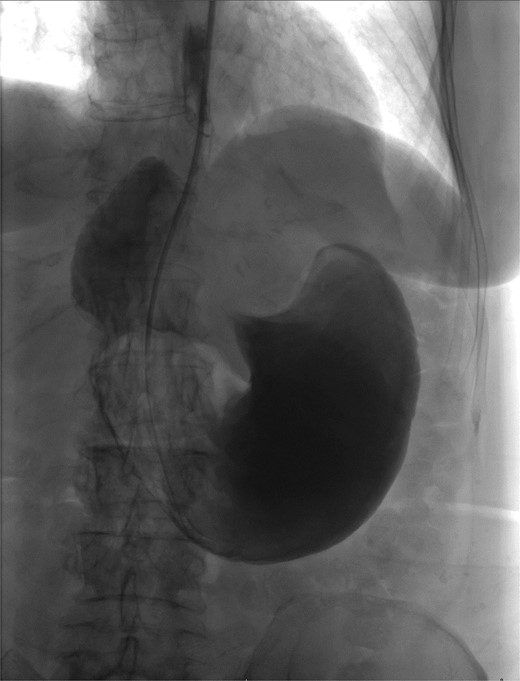

The patient was a 74-year-old female with a history of hypertension, chronic migraines, hiatal hernia repair with Nissen fundoplication repair, and cecal volvulus treated with right hemicolectomy who presented with abdominal pain, nausea, and vomiting. Six months prior, she exhibited symptoms of bloating and nausea, which were treated with oral Reglan with some improvement. She reported vomiting episodes for 2 months that acutely worsened over the 4 days prior to presentation. Examination revealed a soft and mildly distended abdomen with tenderness in the epigastrium and left upper quadrant. Initial vital signs showed a temperature of 36.1°C, blood pressure of 149/88 mmHg, heart rate of 115 beats/min, and oxygen saturation of 95% on room air; tachycardia resolved with resuscitation. Labs were notable for a white blood cell count of 8.8 × 1000/mcL and hemoglobin of 14.2 g/dL. Sodium was 137 mEq/L, potassium was 3.3 mEq/L, and creatinine was 0.75 mg/dL. Computed tomography (CT) of the abdomen and pelvis (Figs 1 and 2) showed gastric volvulus without pneumatosis, significant wall thickening, or distention. Nasogastric tube was placed. An upper gastrointestinal fluoroscopy scan showed no passage of contrast beyond the stomach and demonstrated 90° rotation of the stomach (see Fig. 3). The patient underwent surgery that same day.

Coronal view of CT scan of abdomen and pelvis demonstrating gastric volvulus.